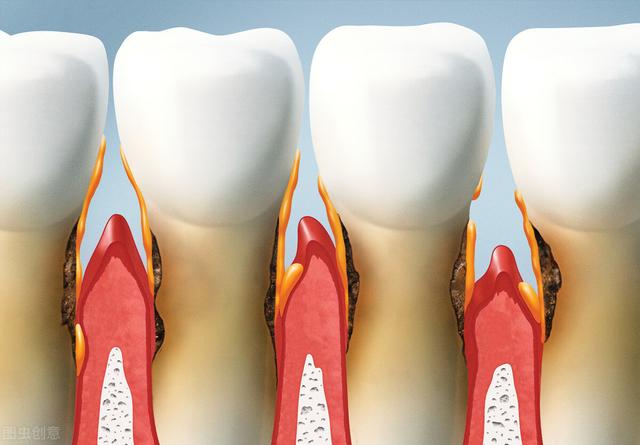

2、潰瘍型と外因型:歯肉癌は臨床的に潰瘍型と外因型があり、潰瘍型が多い。多くは歯間乳頭や歯肉辺縁部から発生する。潰瘍は表在性で赤みを帯び、後に過形成が出現することもある。粘膜骨膜と歯槽骨突起が強固に接着しているため、早期に歯槽骨突起周囲骨膜や骨に浸潤しやすく、歯牙の弛緩をきたし、剥離することもある。

3.広がりと破壊:歯肉癌は頬側(唇側)、口蓋側(舌側)に関係なく、歯間部を通して反対側に広がり、外側には唇と頬溝を、内側には口底と口蓋を侵し、上方には上顎洞底を破壊し、骨を貫通し、上賞洞に入り、上顎洞の二次癌となり、下方には顎骨を侵し、進行すると病理学的骨折を起こすこともある。歯肉癌が骨に浸潤した後、X線フィルムに虫食いのような不規則な吸収が見られることがあるが、これは悪性腫瘍の破壊的特徴である。

歯肉癌の初期症状の検査について、歯肉に小さな潰瘍ができ、表面的で薄紅色で、後に過形成が現れ、その縁に小さな乳頭が突出することがある。X線検査では、悪性腫瘍の破壊的特徴であるミミズ状の不規則な吸収が現れることがある。具体的な症状は以下の通りです:1、歯茎に長い間治らない潰瘍ができ、急速に肥大したり、抜歯後の傷が長く、しこりが突出したりします。2、病巣部の歯が緩み、痛みます。3、臼歯後方や咽頭部に発生すると、口が開きにくくなり、下歯槽神経に影響すると、下唇がしびれます。4、頸部リンパ節の腫大です。5、レントゲン検査で、顎骨が「扇形」の骨破壊の形をしています。6、レントゲン検査で、顎骨が「扇形」の骨破壊の形をしています。レントゲン検査では、顎骨は「扇形」の骨破壊であり、縁はミミズ状である。6、病理組織学的検査で診断が確定する。

歯肉癌の初期症状は、口腔癌の大部分と同様に潰瘍として現れ、一般に人はこのような癌性潰瘍を正常な状態の口内炎と混同しやすい。歯肉癌の初期症状は主に上顎部、特に臼歯部や前歯列部(6歳歯周辺)に発生し、初期症状の特徴としては、痛みはないが急速に発生し、潰瘍の根元や周囲が硬くなり、縁が堤防状に隆起し、次いで表面がカリフラワー状に変化する。

がんが神経に浸潤したり、二次感染を起こしたりすると自発痛があり、がんが歯槽骨に浸潤して破壊されると歯が緩んで痛み、がんが口腔底や頸部、あるいは口を閉じる筋肉群に浸潤すると開口制限が起こり、二次感染や組織の壊死が起こると特殊な悪臭がする。

初期の歯肉癌、特に歯肉縁や歯間乳頭に限局している場合は、歯肉炎や歯周炎と誤診されやすい。第二に、初期の潰瘍性病変、特に痛みを伴うびまん性の歯肉縁は、歯肉結核と誤診されることもある。上記の疾患の臨床診断では、歯肉癌の可能性に注意する必要があり、X線検査では、顎骨の「扇形」の骨破壊がみられ、ミミズ状の縁が認められる。